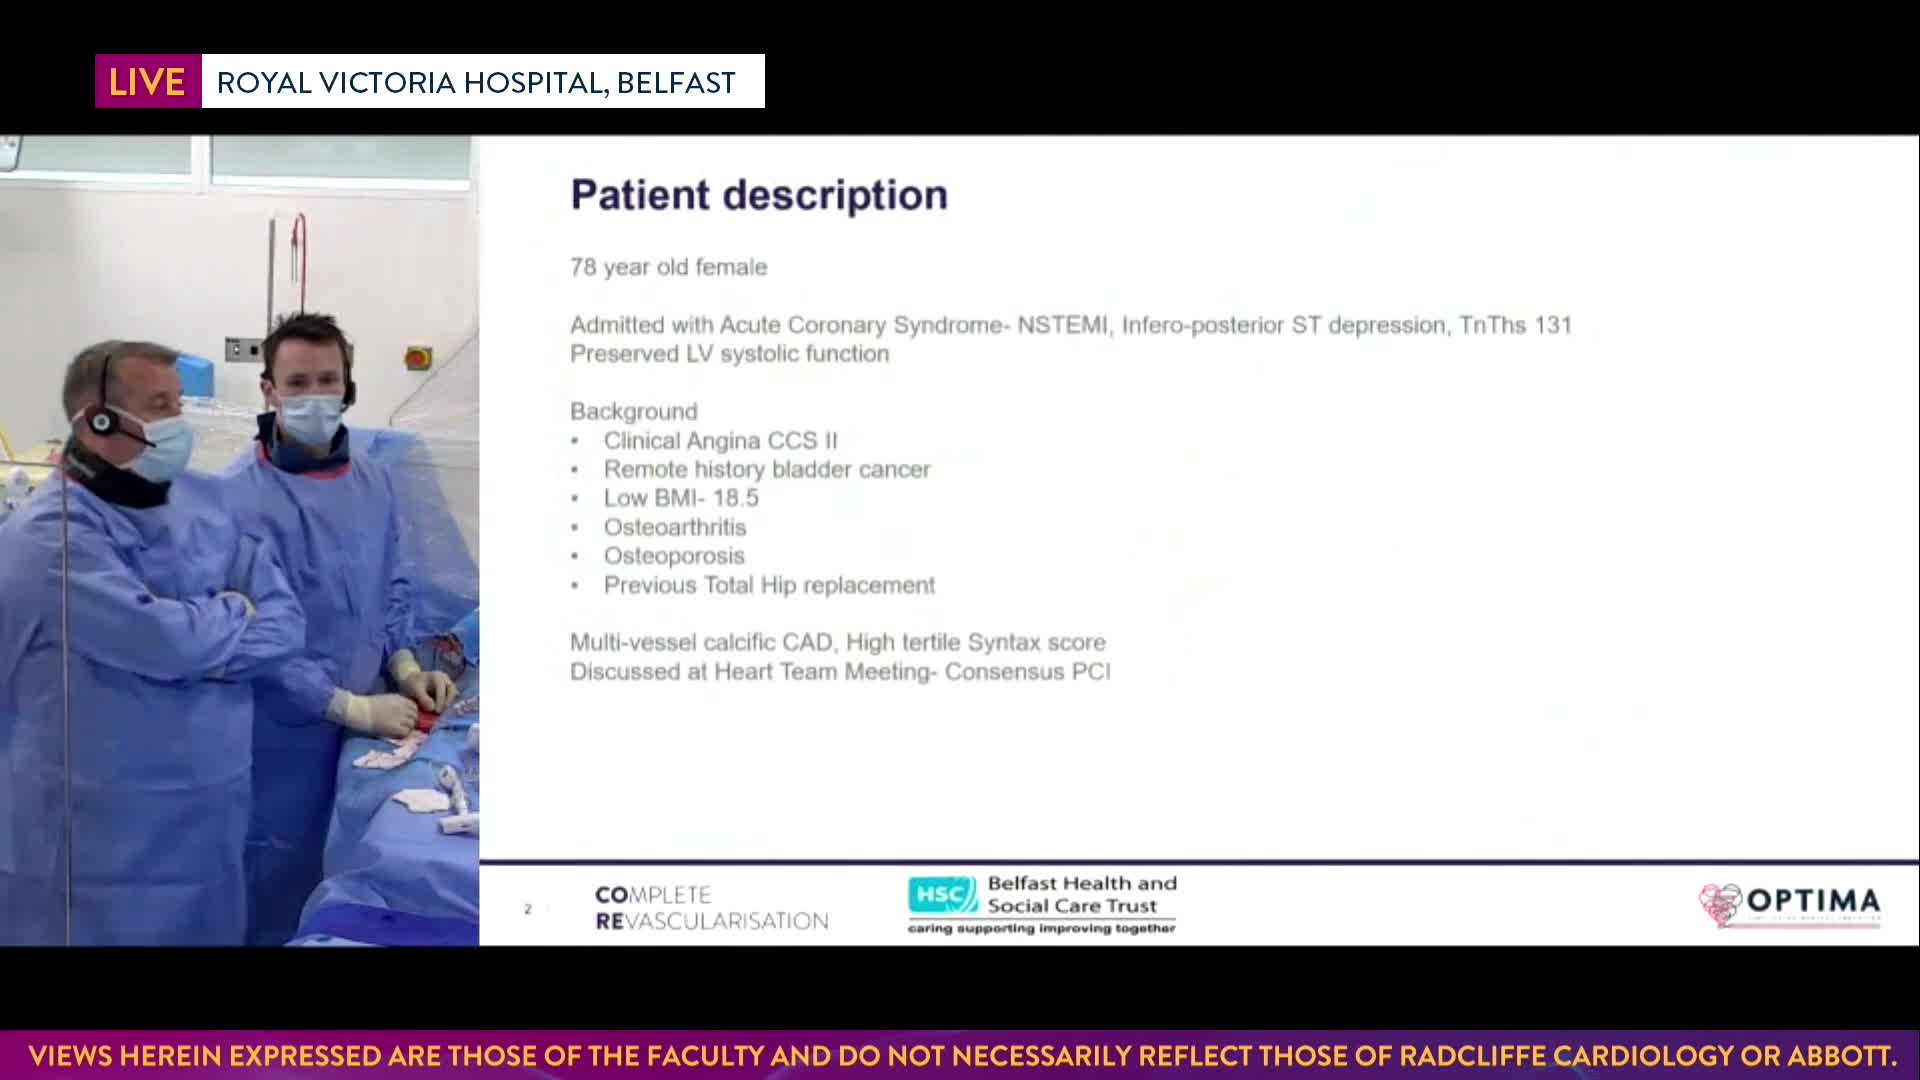

Session 4: High-risk and complex – too tough to treat?